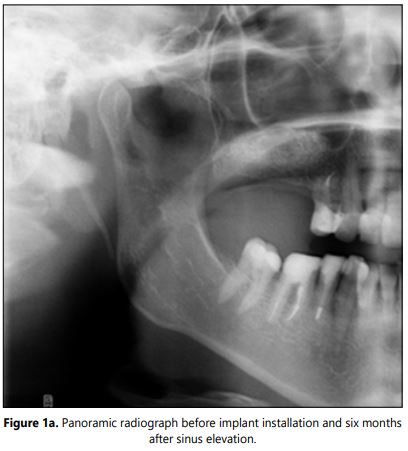

Radiographic examination: The CBCT or panoramic X-rays were performed pre-surgically and before the implant placement to evaluate the bone formation (Figures 1 and 1a). Intraoral X-rays were accomplished six months after implant placement and then annually to asses marginal bone loss. The success rate was determined using the Albrektsson et al. criteria [18].

Radiographic examination: At the time of the implant placement the mean of the bone gain was 11.91 mm ± 2.80 mm. The new bone volume in all the cases allows the subsequent implant installation. At the 5-year follow up examination the marginal bone reduction showed minor changes.